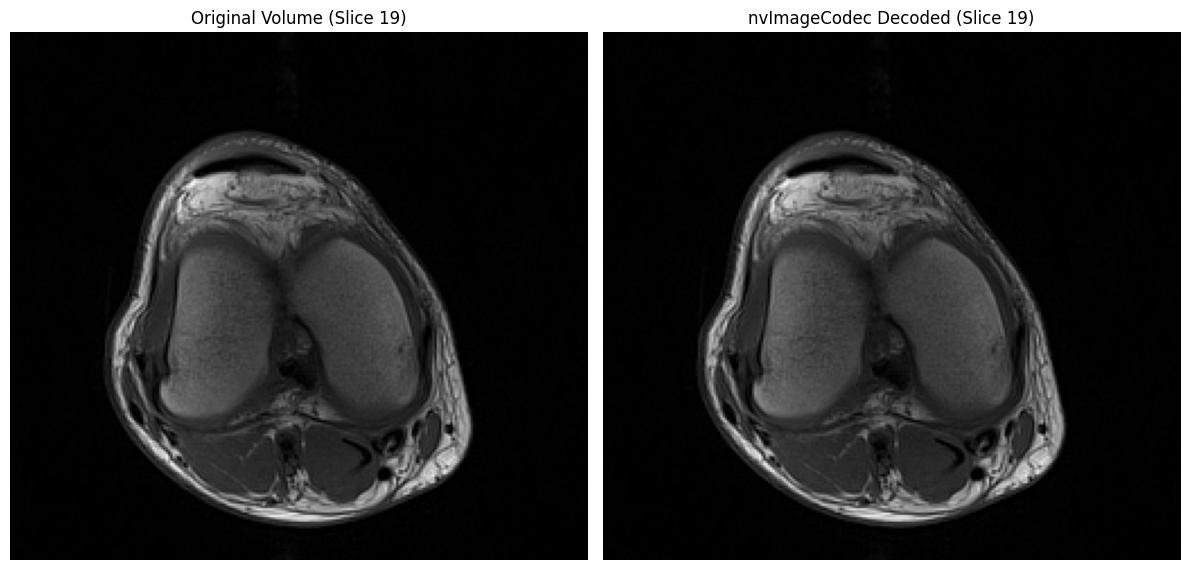

# Visual comparison

mid_idx = len(volume) // 2

fig, axs = plt.subplots(1, 2, figsize=(12, 6))

axs[0].imshow(volume[mid_idx], cmap='gray')

axs[0].set_title('Original Volume (Slice {})'.format(mid_idx))

axs[0].axis('off')

axs[1].imshow(nvimg_decoded_cpu[mid_idx], cmap='gray')

axs[1].set_title('nvImageCodec Decoded (Slice {})'.format(mid_idx))

axs[1].axis('off')

plt.tight_layout()

plt.show()

⏱️  pydicom decode time:     0.0675s (1.78 ms/file)

⏱️  nvImageCodec decode time: 0.0367s (0.96 ms/file)

🚀 Speedup: 1.84x faster

✓ All decoded slices match original